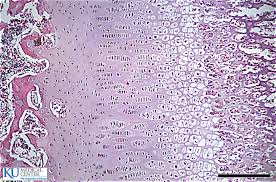

| Epiphyseal Plate Growth (phases from right to left) 1. resting zone 2. proliferation (mitosis) 3. hypertrophic (cells enlarge) 4. calcification 5. ossification | |